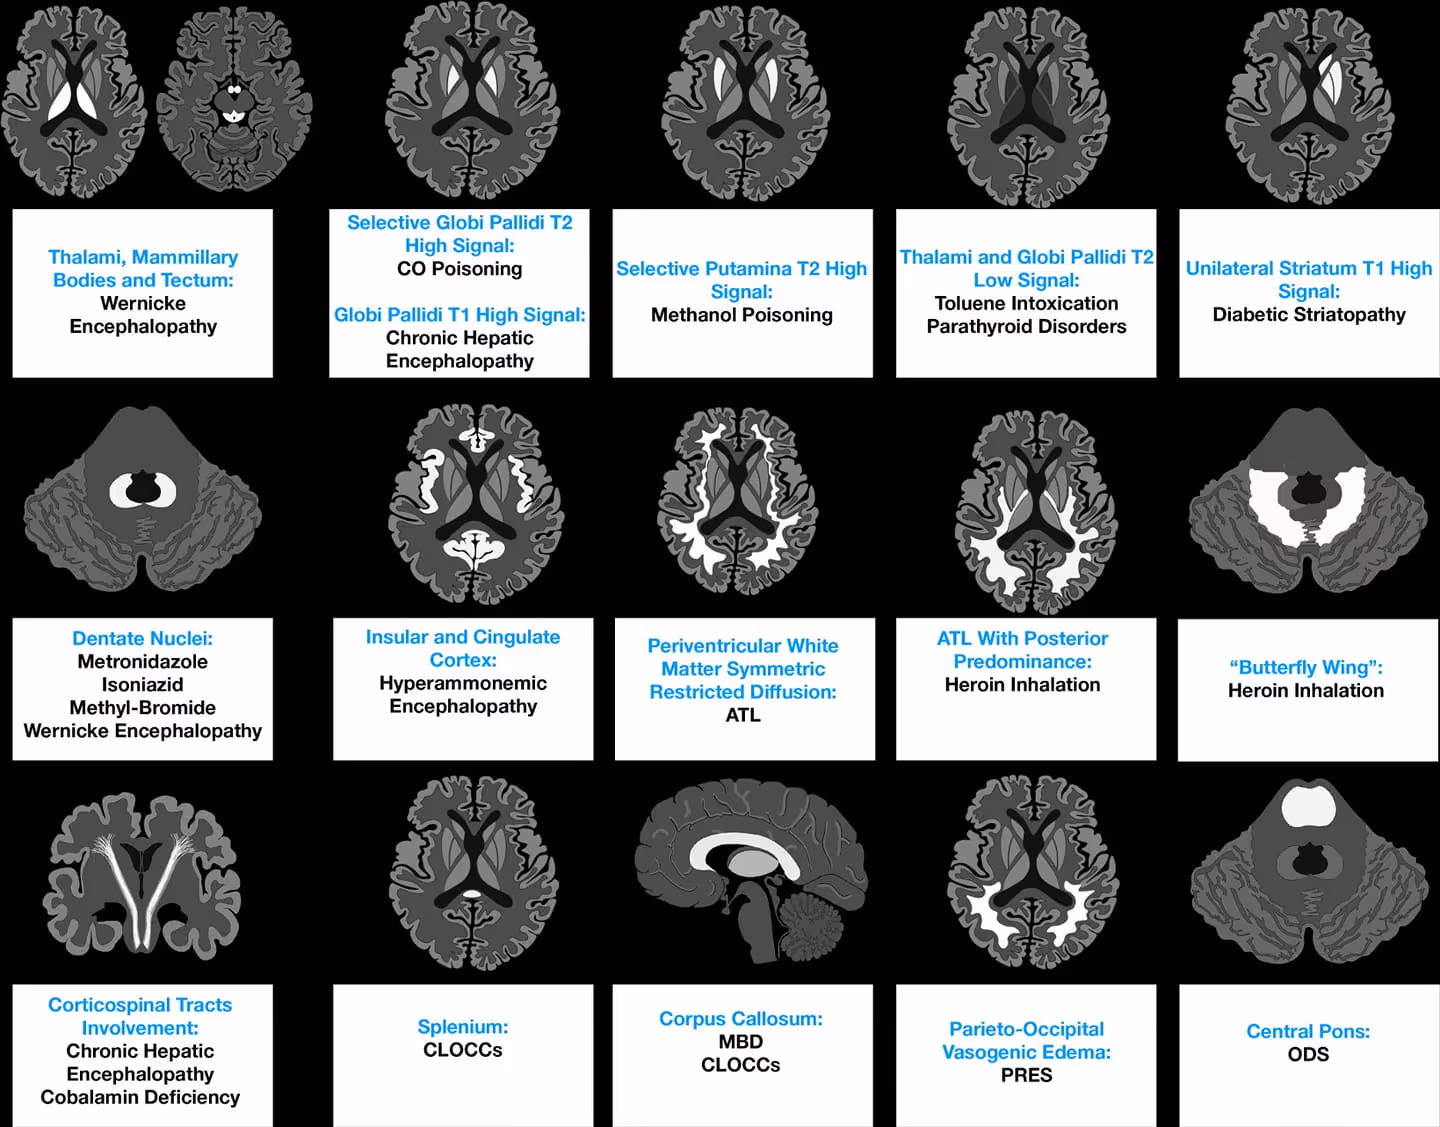

Imaging Patterns of Toxic and Metabolic Brain Disorders